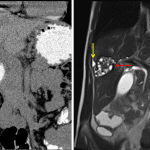

- Complex lesion in the right hepatic lobe measuring 5.2 x 4.5 x 4.2 cm with a hyperechoic rim, multiple rounded internal hypoechoic areas, and no internal Doppler flow

Hydatid cyst

Complex lesion in the right hepatic lobe measuring 5.2 x 4.5 x 4.2 cm with multiple internal cystic areas and no internal vascularity. Differential considerations include a multilocular pyogenic abscess, hydatid cyst, and necrotic/cystic neoplasm.

Mild extrahepatic biliary duct dilation without obstructing mass or stone identified. MRCP or ERCP could provide further evaluation.